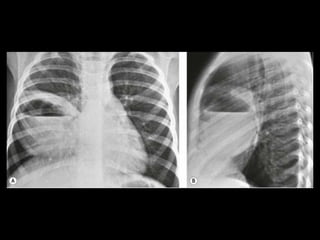

Malformação arteriovenosa(MAV) MAV congênitas: fístulas vasculares com comunicação entre a artéria e a veia pulmonar(95%) ou de uma artéria sistêmica e a veia pulmonar com by-pass do leito capilar; Cerca de 50% das MAVs estão associadas com Síndrome de Rendu-Osler-Weber(teleangiectasia hemorrágica hereditária); O diagnóstico costuma ser bem direto pela TC;

Malformação arteriovenosa(MAV) TC:o aspecto típico é de uma massa regular, lobulada, redonda ou oval, ou até o de uma formação serpenginosa, com menos de 1 cm a vários cm de tamanho, associada a uma artéria nutriz visivelmente aumentada e uma veia de drenagem alargada; Uma ANGIO-TC geralmente faz o diagnóstico; Tratamento pode ser realizado com terapia embólica.